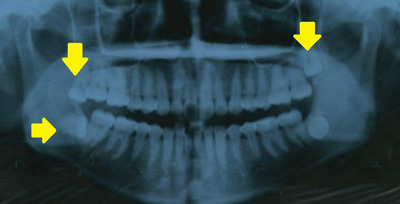

パノラマ・レントゲン写真に写っている親知らず

黄色い矢印の先